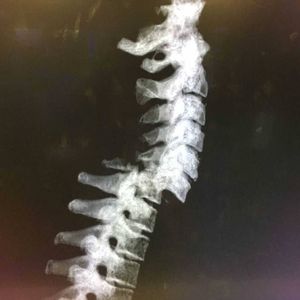

Can you even imagine how painful this might have been?? This is a fracture of the vertebral column due to fall from a ladder...i dont know how high was the ladder...maybe it was ladder to heaven(south park reference) Usually vertebral column innjuries are very serious due to the outcome which could include paralysis below the level of the fracture...so be careful whenever you do any action involving ladders. @medicalcortex